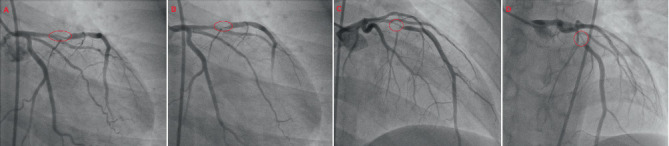

Overconsumption of energy drinks containing high levels of caffeine has been increasingly linked to cardiovascular morbidity and mortality. This case report describes a 24-year-old Caribbean-Black male with no prior comorbidities who experienced an aborted sudden cardiac death (SCD) after a recent energy drink binge a few hours prior to his ventricular fibrillation (VF) cardiac arrest. Primary percutaneous coronary intervention (PPCI) was successfully performed for a dreaded widowmaker lesion, thought to have arisen as a sequela of his excessive energy drink intake. The clinician should be cognizant of the major adverse cardiovascular events (MACEs), such as acute coronary syndromes (ACSs) and lethal arrhythmias, implicated with energy drink consumption.